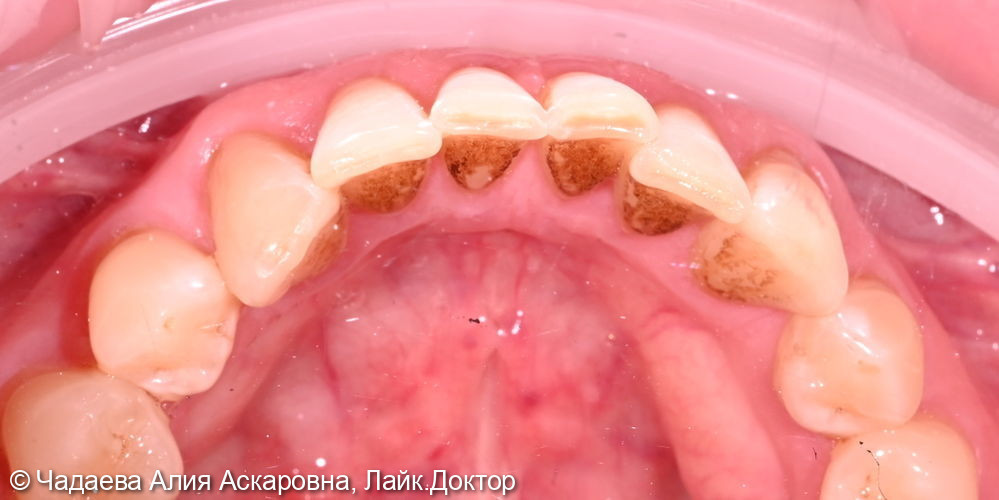

Пациент обратился с жалобами на наличие надесневых зубных отложений и пигментного налета. При проведении осмотра было выявлено наличие надесневых отложений и пигментного налета.

Проведена комплексная профессиональная гигиена полости рта по швейцарскому протоколу GBT. Удаление зубных камней и зубного налета аппаратом Air-flow, полировкаПоказать полностью... зубов, фторирование (покрытие фторлаком).